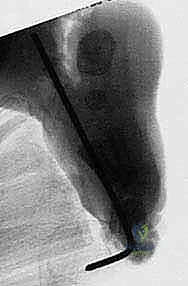

5. التثبيت بأسلاك كيرشنر (K-wires Fixation):

بعد استعادة الوضع التشريحي المثالي للقدم، يقوم الدكتور هطيف بتثبيت العظام في وضعها الجديد باستخدام أسلاك معدنية دقيقة (أسلاك كيرشنر). تمر هذه الأسلاك عبر المفاصل لضمان عدم تحركها أثناء فترة الالتئام.

6. الإغلاق التجميلي والجبس: